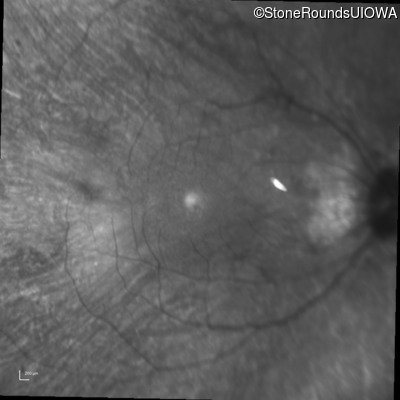

Infrared Fundus Photograph - Right - 20/30 +2

Exemplar

Infrared Fundus Photograph - Left - 20/20 -2